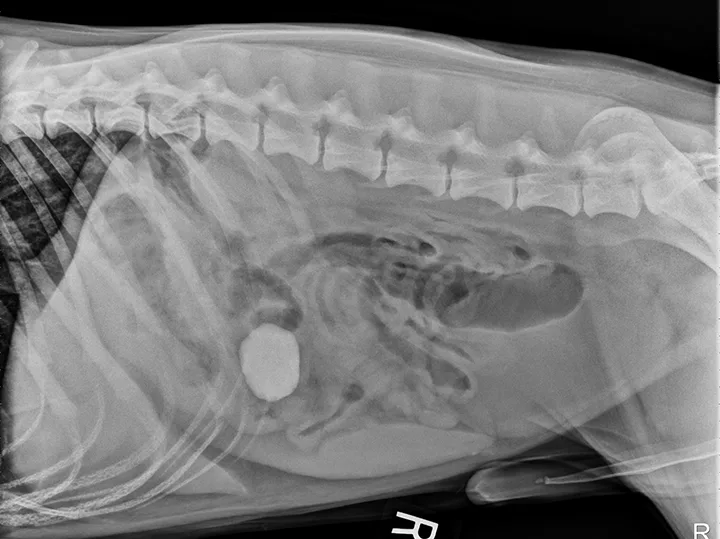

FIGURE 1A

Lateral view. Abdominal radiographs showing a rock foreign body that appears to be located in the small intestine. No small intestinal foreign body could be located on abdominal ultrasound; however, a shadowing foreign object was possibly located in the stomach.